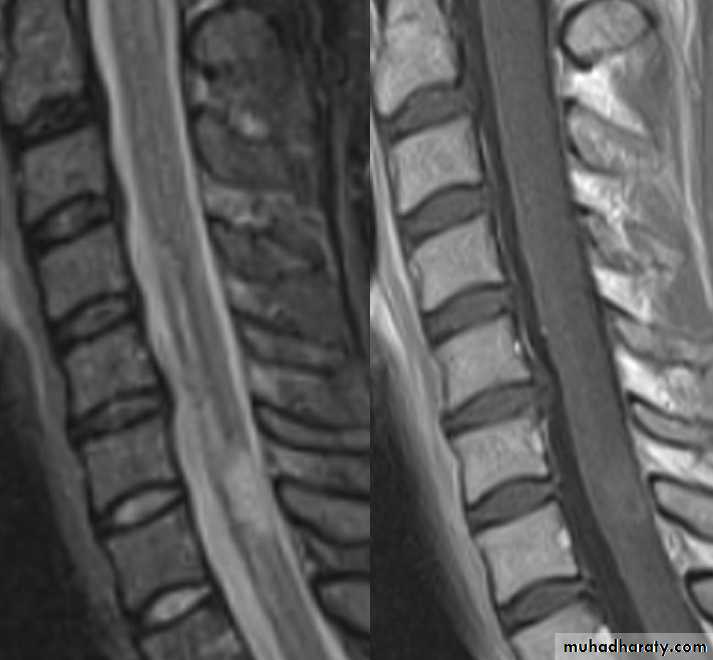

MRI FINDINGS

Patchy areas of white matter in paraventricular cerebral areas

Lesions in cerebellum/brainstem/ cervical and thoracic spinal cord

Gadolinium enhancement identifies active lesions